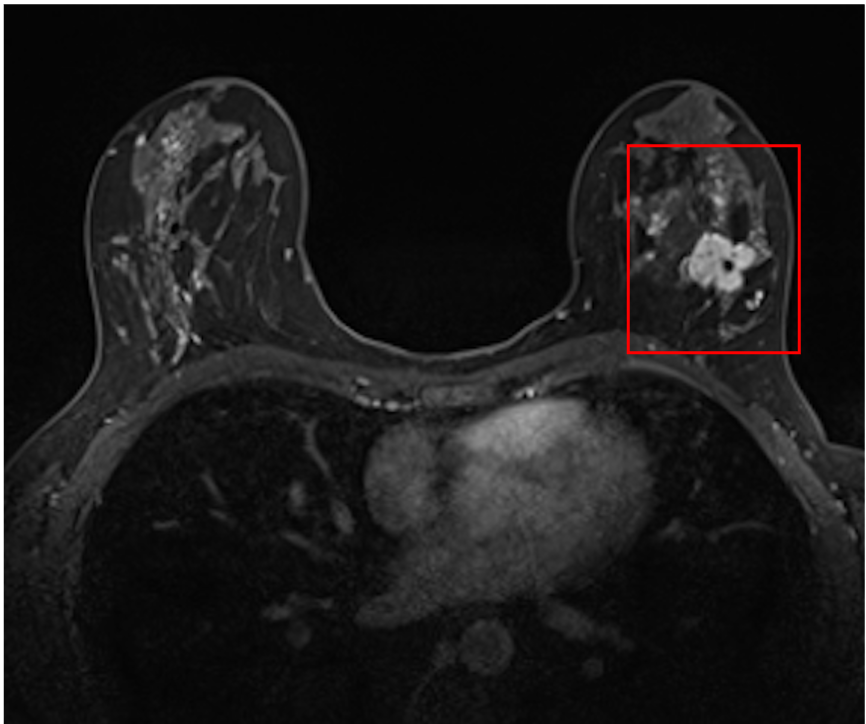

1) Primary Tumour Segmentation in DCE-MRI

Participants will use the largest homogenized DCE-MRI dataset to date, featuring 1,506 annotated scans and key clinical variables, and validate their models across 574 external cases from diverse imaging protocols and settings. The challenge emphasizes generalizability and fairness, ensuring equitable model performance across demographic subgroups, and aims to optimize breast cancer treatment and surgical planning.